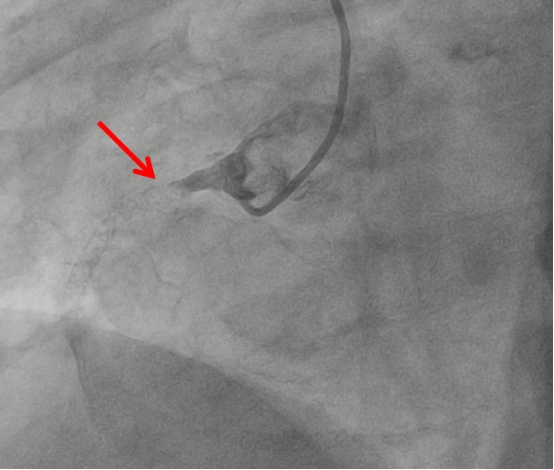

2026-01-09五院技术 | 青少年脑梗之谜,谁是“元凶”?

高一学生小朱(化名)在一次体育课剧烈运动后突发持续头晕,当地医院诊断为“急性脑梗死”。青少年脑梗实属罕见,当地医院初步检查怀疑病因为“卵圆孔未闭”,建议转至上级医院进行手术治疗。